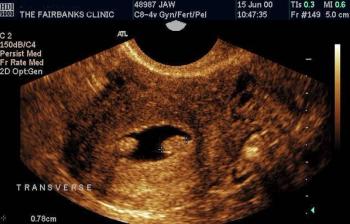

A 29-year-old gravida 10, para 3 (1 term gestation, 1 preterm gestation of twins, 1 stillbirth at 5 months, 2 spontaneous abortions, and 4 elective abortions) presented to the clinic at about 5 weeks’ gestation with abdominal pain and vaginal bleeding. She described the pain as sporadic, mostly on the left side, exacerbated by movement, and resolving with rest, and the bleeding as initially intermittent but then heavier “like a period.”

Implantation in the scar of a previous Cesarean is thought to be the rarest of ectopic pregnancies. With the increasing numbers of Cesareans performed, scar implantation may become more frequent as well. We present an illustrative case.